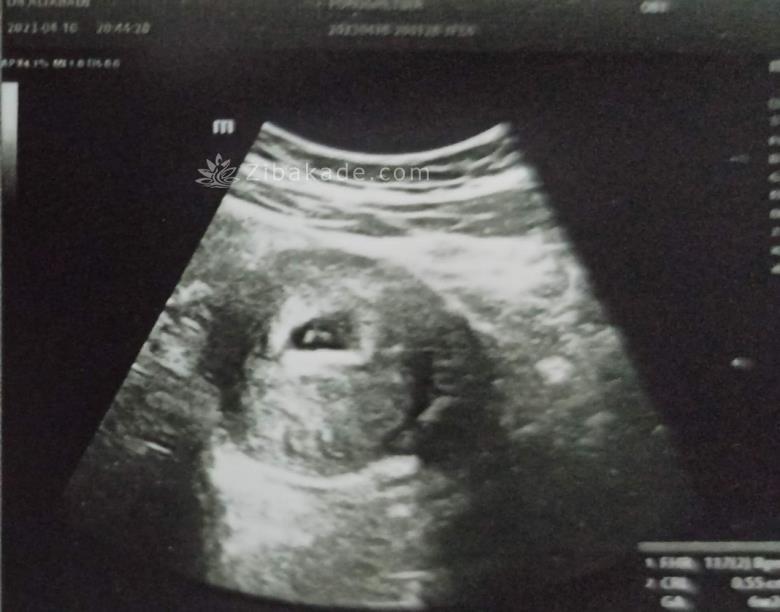

سلام دوستان من سونوگرافی هفته ۶ بارداریمو هنوز به دکترم نشون ندادم و از طرفی تو عکس سونو انگار تو ساک بارداریم دو تا جنین هست و این شک که ممکنه دوقلو باشه رو همسرم اول به دلم انداخت میشه نگاه کنین و نظر بدین؟